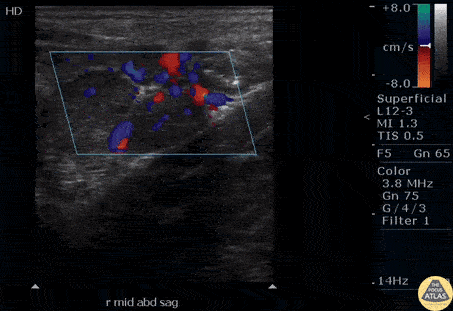

A young child presented to the ED with RLQ abdominal pain and a low-grade fever. Bedside ultrasound revealed enlarged, hypoechoic mesenteric lymph nodes with surrounding vascularity indicative of mesenteric adenitis. Be sure to rule out appendicitis. Image courtesy of Robert Jones DO, FACEP @RJonesSonoEM Director, Emergency Ultrasound; MetroHealth Medical Center; Professor, Case Western Reserve Medical School, Cleveland, OH View his original post here